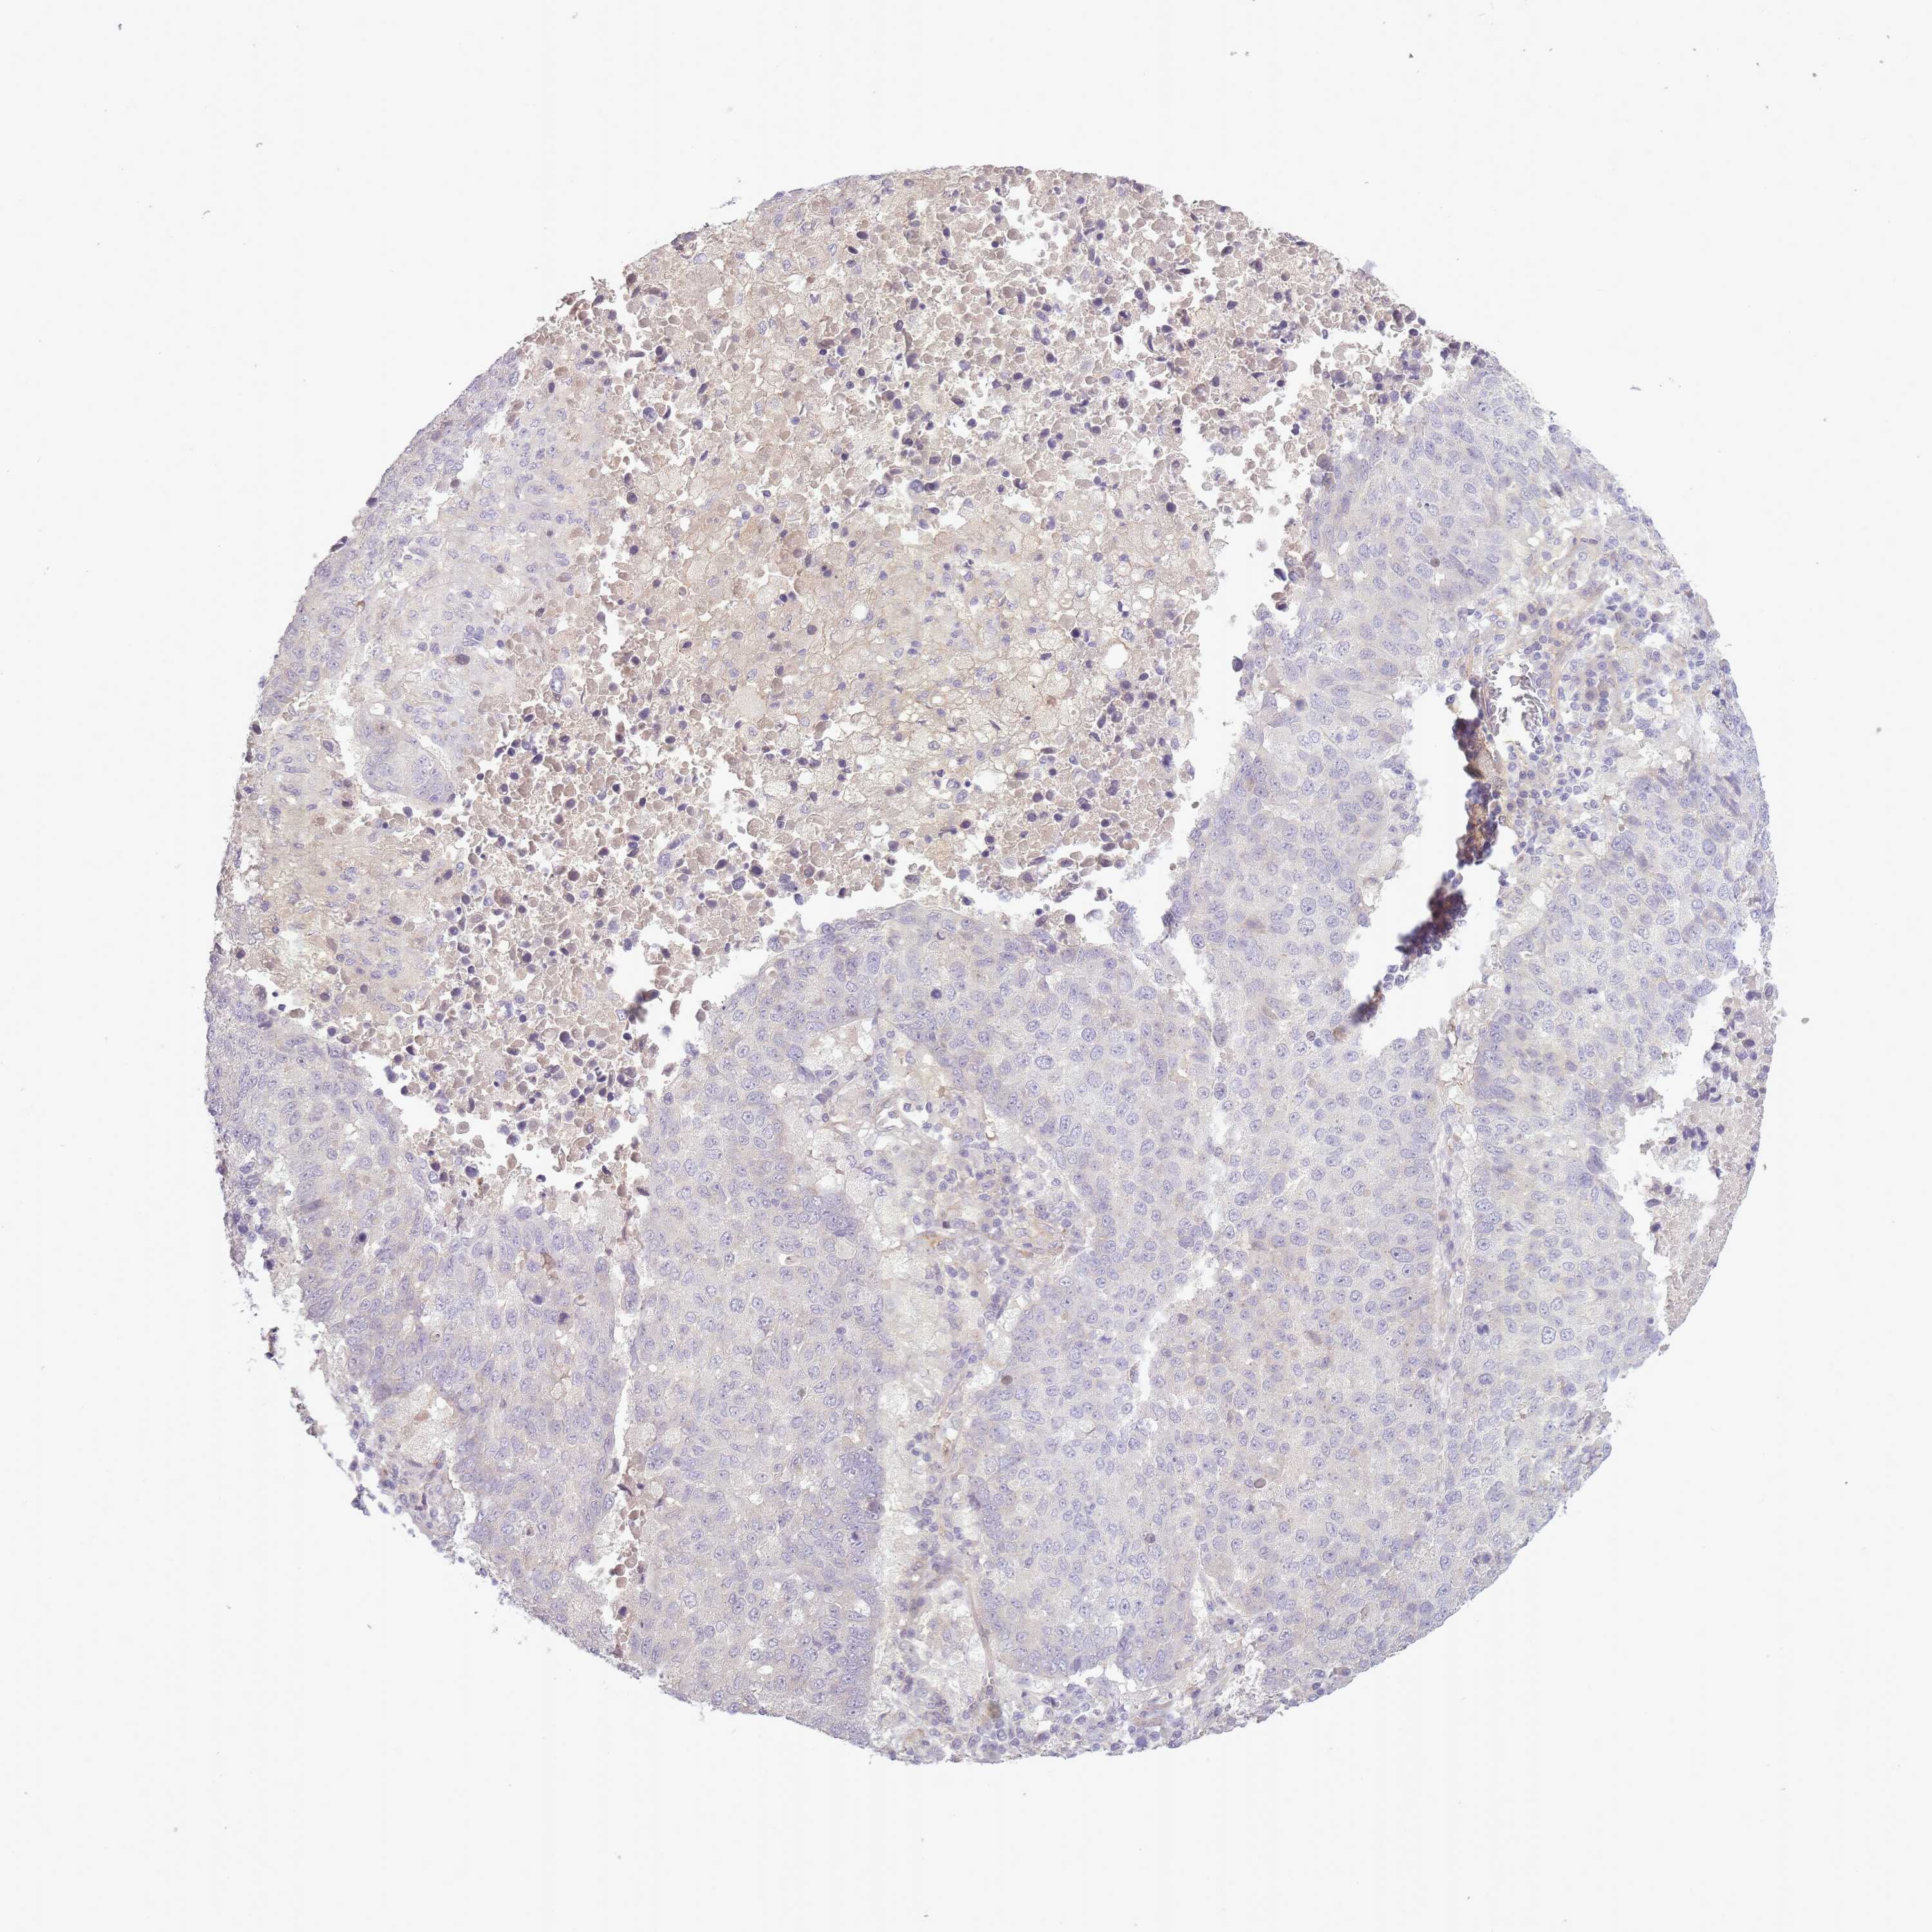

SLC8A2

CANCER LUNG CANCER Show tissue menu